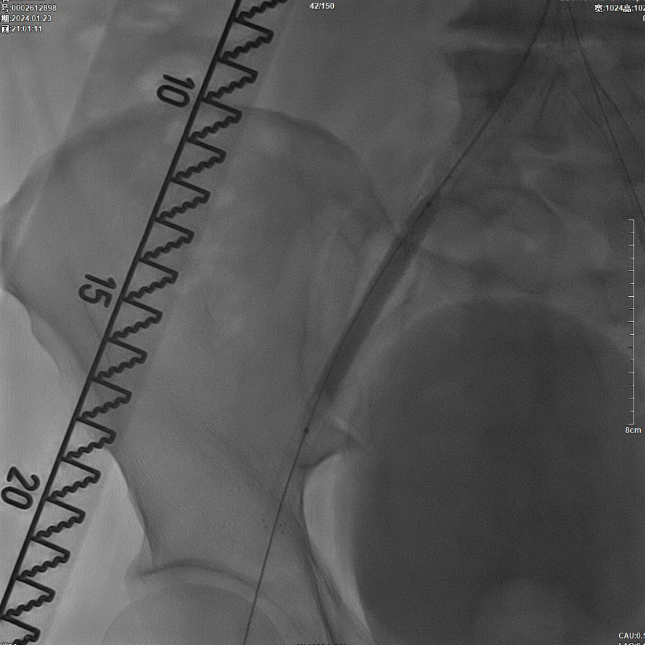

术前影像学评估:CTA显示腹主动脉下段闭塞,双侧髂总、髂外动脉支架内闭塞,右侧股动脉亦存在闭塞。结合急性加重病史,考虑为“基础狭窄+急性血栓形成”,不排除栓塞可能。

鉴于患者腹主动脉末端存在支架且多部位闭塞的复杂病变特征,术者团队决定采用CERAB技术实施腔内治疗,并选择双侧股动脉穿刺逆行开通路径以提高手术成功率。

在超声引导下,成功完成双侧股总动脉穿刺。通过导管配合超滑导丝,顺利通过病变区域进入腹主动脉下段,造影明确腹主动脉下段及双侧髂动脉完全闭塞的病变范围与程度。